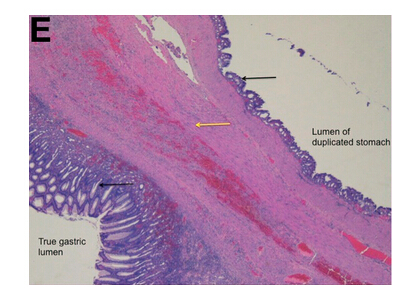

術(shù)中發(fā)現(xiàn)可疑病變具有定義不明的外科平面和顯著的周圍纖維化,最終行空腸食管Roux-en-y吻合術(shù)。組織學(xué)檢查(圖D)和顯微鏡標(biāo)本(圖E)顯示正確診斷。

令人驚訝的是,胃大部切除標(biāo)本(圖D)檢查發(fā)現(xiàn)在疑似腫瘤的胃壁區(qū)域內(nèi)有扁平囊。這一扁平囊可以拉伸到9×8×4.5cm。胃囊與真實(shí)胃腔之間有一處共同的壁。通過(guò)此壁的組織學(xué)切片(圖E)顯示了分隔壁兩側(cè)的平滑肌細(xì)胞層和胃黏膜。這排除了GIST,證實(shí)胃重復(fù)畸形的診斷(GDC)。胃重復(fù)畸形是一種罕見(jiàn)的先天性異常,僅占胃腸道所有重復(fù)囊腫的4%至9%。大多數(shù)病例報(bào)告發(fā)生在兒童中且位于胃大彎處。GDC有以下3個(gè)特點(diǎn):(1)囊腫的壁與胃壁相連,(2)囊腫由平滑肌包圍,通過(guò)肌肉與胃壁相連,(3)囊壁排列有胃上皮或其它類型的胃黏膜。